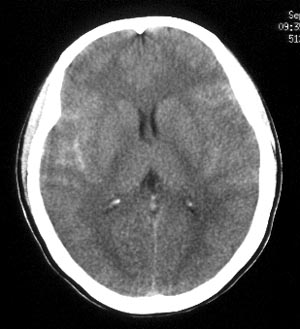

女性,36岁。头部外伤半小时,现觉头痛,有呕吐,无昏迷。

ct平扫:双侧脑沟、脑裂见密度增高,双侧大脑半球及颅后窝脑实质未见异常密度改变。

ct诊断:蛛网膜下腔出血。